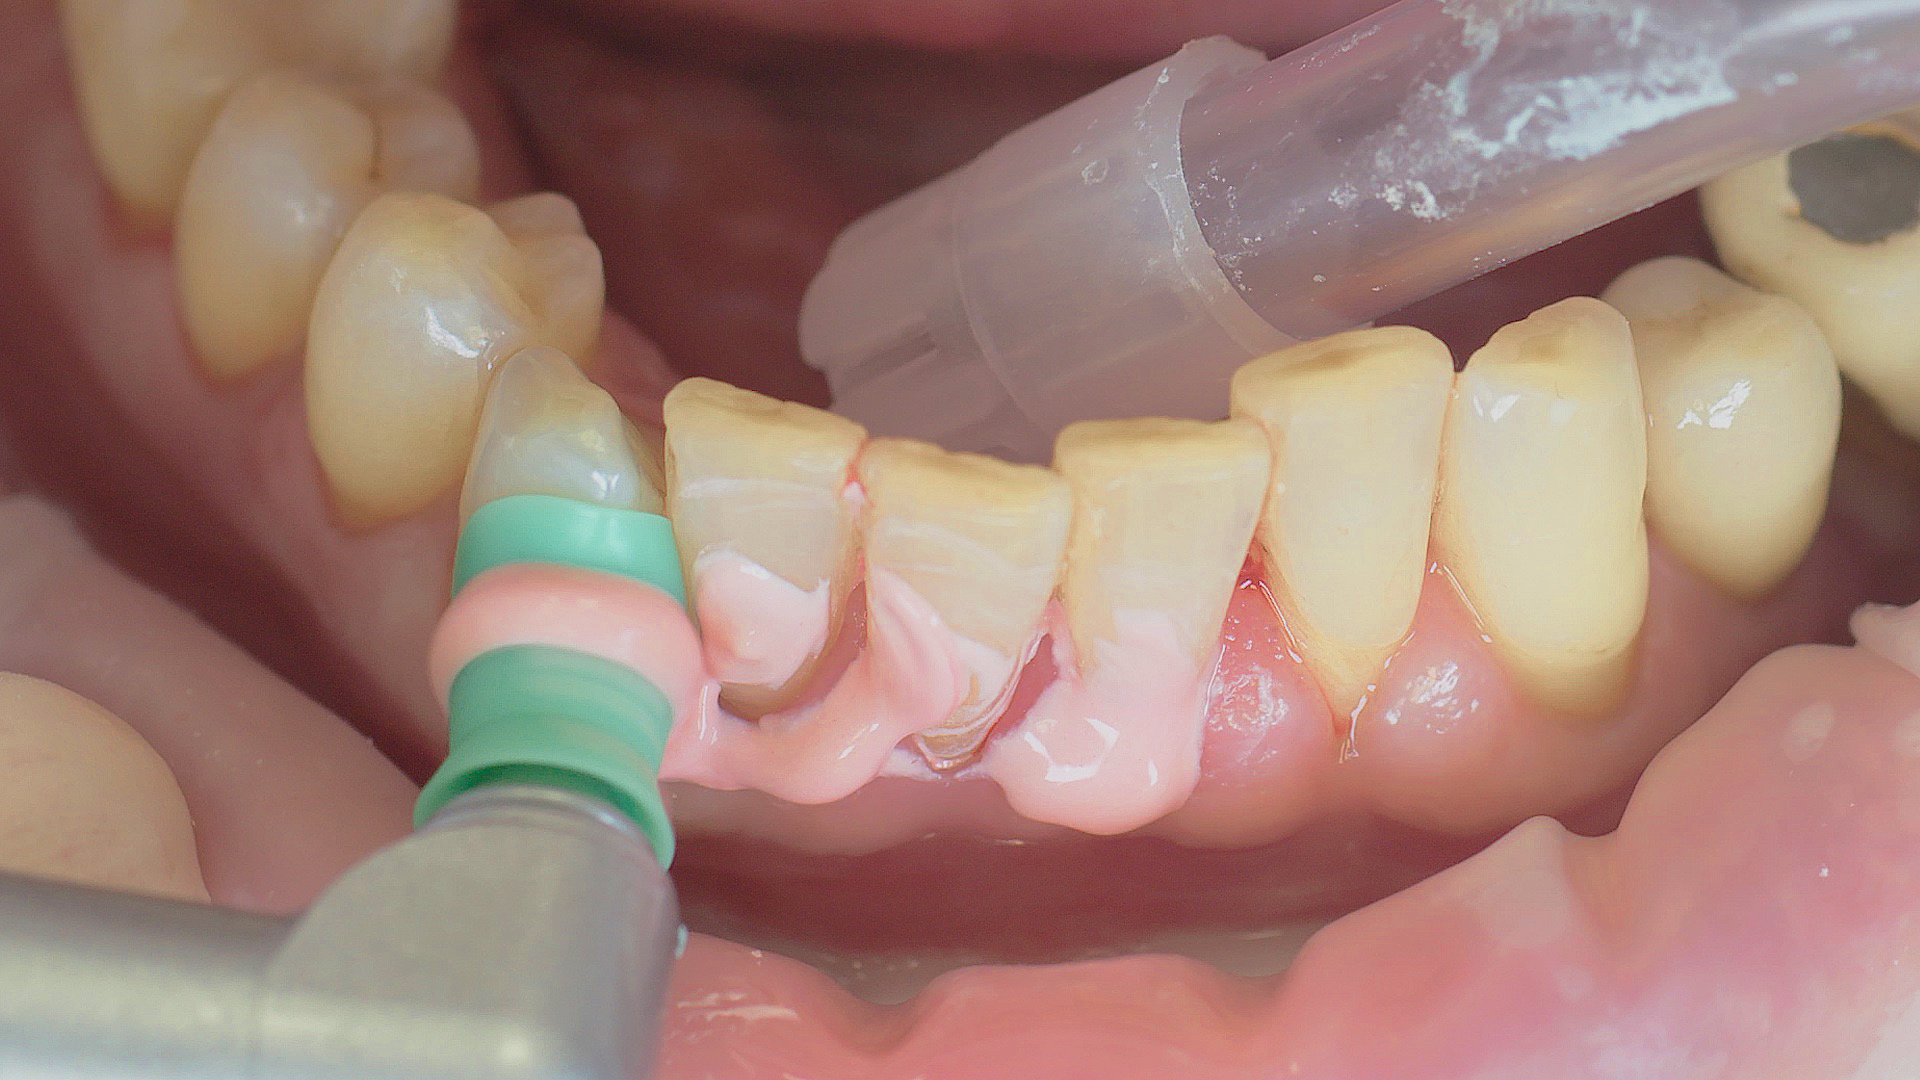

Implants and superstructures can be successfully cleaned with ultrasonic devices and special plastic instruments

Fig. 3: Implants and superstructures can be successfully cleaned with ultrasonic devices and special plastic instruments during postoperative care or non-surgical therapy.

Healthy peri-implant tissue does not show any signs of redness, swelling or bleeding, neither does it secrete pus when probed.[5] Based on the consensus document, Prof. Giovanni Salvi explained the importance of regu- lar probing — preferably with a flexible probe, as implant components often tend to obstruct the procedure.[5] In the case of mucositis or initial peri-implantitis already being present, the non-surgical removal of hard deposits and biofilm should be attempted first. For this purpose, ultra- sonic power and special instruments designed to protect the implant should be employed (Fig. 3; piezo scaler Tigon+ with 1I, W&H). In case of no remission, the recall frequency needs to be increased. However, specific recommendations, applicable to individual cases, are not yet available in this context.[15]